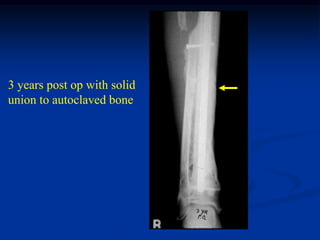

3 years post op with solid

union to autoclaved bone